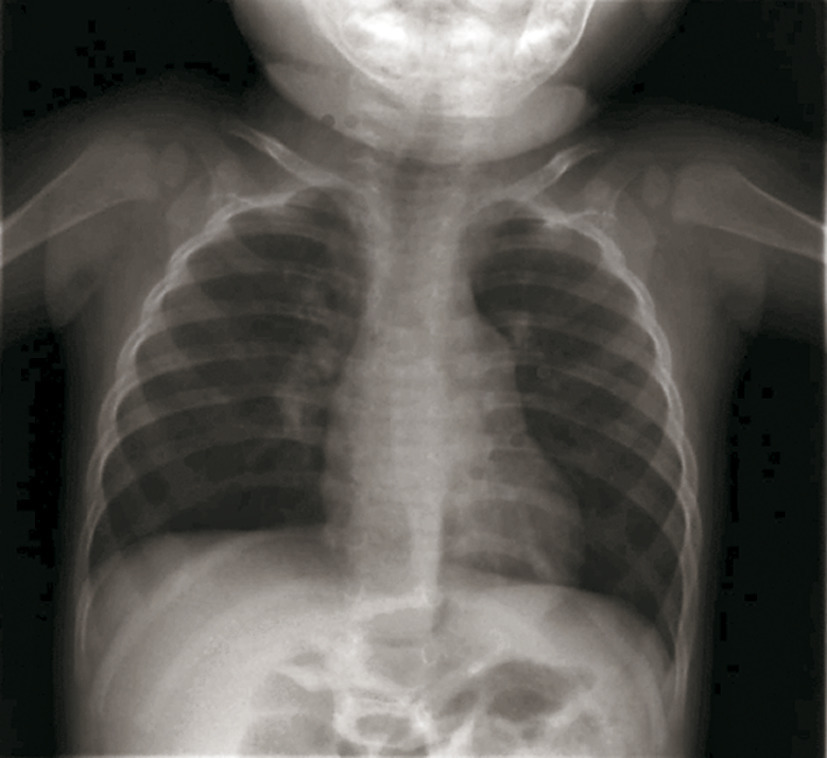

Radiographie thoracique :

– réservée aux formes sévères hospitalisées ou d’évolution inhabituelle (fébrile ou traînante) :

– « syndrome bronchique » ;

– distension avec hyperclarté des 2 champs pulmonaires, horizontalisation des côtes (plus de 9 espaces intercostaux visibles) et aplatissement des coupoles diaphragmatiques (fig. 1) ;

– atteinte alvéolaire avec opacités floconneuses périphériques ;

– atélectasie segmentaire ou lobaire en cas de bouchons muqueux (craindre une surinfection bactérienne) [fig. 2] ;

– plus rarement, aspect d’emphysème lobaire, médiastinal ou pneumothorax.